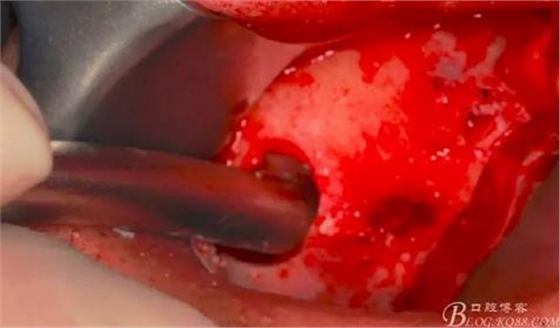

用骨粉充填器植入骨粉。

14,15牙位植入兩顆植體,6,7牙位骨高度嚴(yán)重不足,且骨密度低,無法給植體提供良好的初期穩(wěn)定性,需二期植入。13牙位骨寬度不足,沒有植骨、植植體,修復(fù)時用后面4顆連冠加一顆3的游離臂是沒有問題的。當(dāng)然這里我們不去討論這個方法的合理性,我們今天的話題是改良式外提升技術(shù)的應(yīng)用。